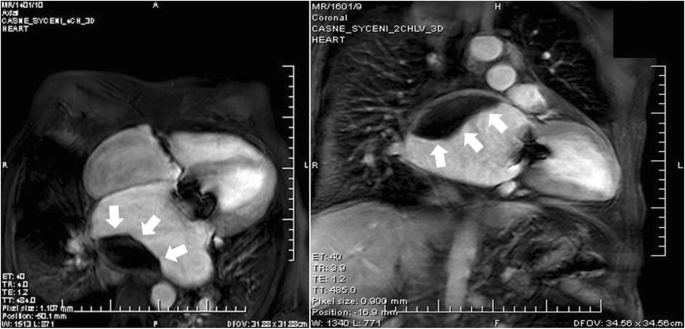

After 3 months post-surgery, the patient came in for his regular check-up, without any cardiac symptoms and with effective INR (2.13). A large sessile intra-atrial mass on the posterior wall of the giant LA was detected by TTE (Figure 2). The echocardiograph could not exclude the suspicion of mitral bioprosthesis dysfunction due to limited leaflet opening and increased LA/LV maximal gradient from the postoperative values from approximately 2-3 mmHg to 7-8 mmHg. Within a differential diagnostic procedure to differentiate possible thrombus from other intra-atrial masses (especially myxomas), CMRI was performed according to the standard protocol using a 1.5T scanner (Ingenia, Philips Medical Systems, Best, The Netherlands). Early gadolinium enhancement (EGE) images in both long-axis views and short axis views were acquired 1 minute after an intravenous bolus of 0.2 mmol/kg of the gadolinium-based contrast agent gadobutrol (Gadovist, Bayer-Schering Pharma, Germany). Extreme dilatation of LA (91x84mm) and a large sessile thrombus (60x30mm) on the posterior wall of the LA were confirmed by EGE images [10] (Figure 3).